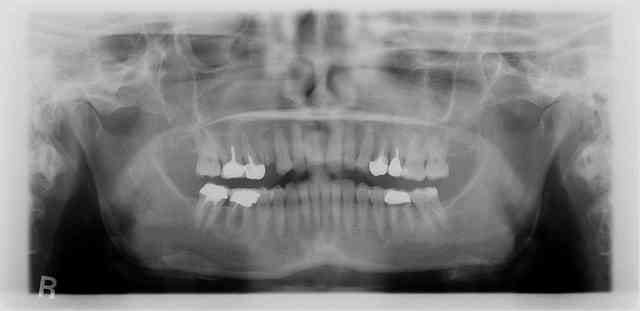

pose d'un axiom en 4*12 en juillet en sous crestal comme il le faut.

et aujourd'hui raido début de cratérisation : petite mais existante;

pour la forme et le fond pano avant retro à la pose et rétro aujourd'hui

prévu implant en 36 et l'endo de 15 avait été reprise avant pour être refaite simultanément je connais les critiques nonoliennes.